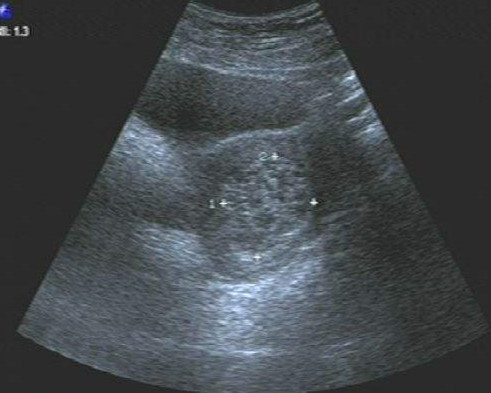

直到最近,刘大姐感下腹部疼痛不适,近日疼痛症状加重,便来到医院就诊。通过检查发现,她子宫内的“T型”节育环已经移位到了膀胱,并在膀胱“产子”——膀胱结石,原来疼痛是由于膀胱结石引起。

泌尿外科医生为其做了“膀胱切开取石”手术,取出一“鸡蛋”大小的石头,切开石头一看节育环就藏在里头。株洲市中心医院妇科副主任徐琼表示,宫内节育环有“服役期”,放环后并非一劳永逸,还需要节育妇女定期到医院检查,如发现异常要及时处理,否则节育环可能“移居”而造成严重后果。